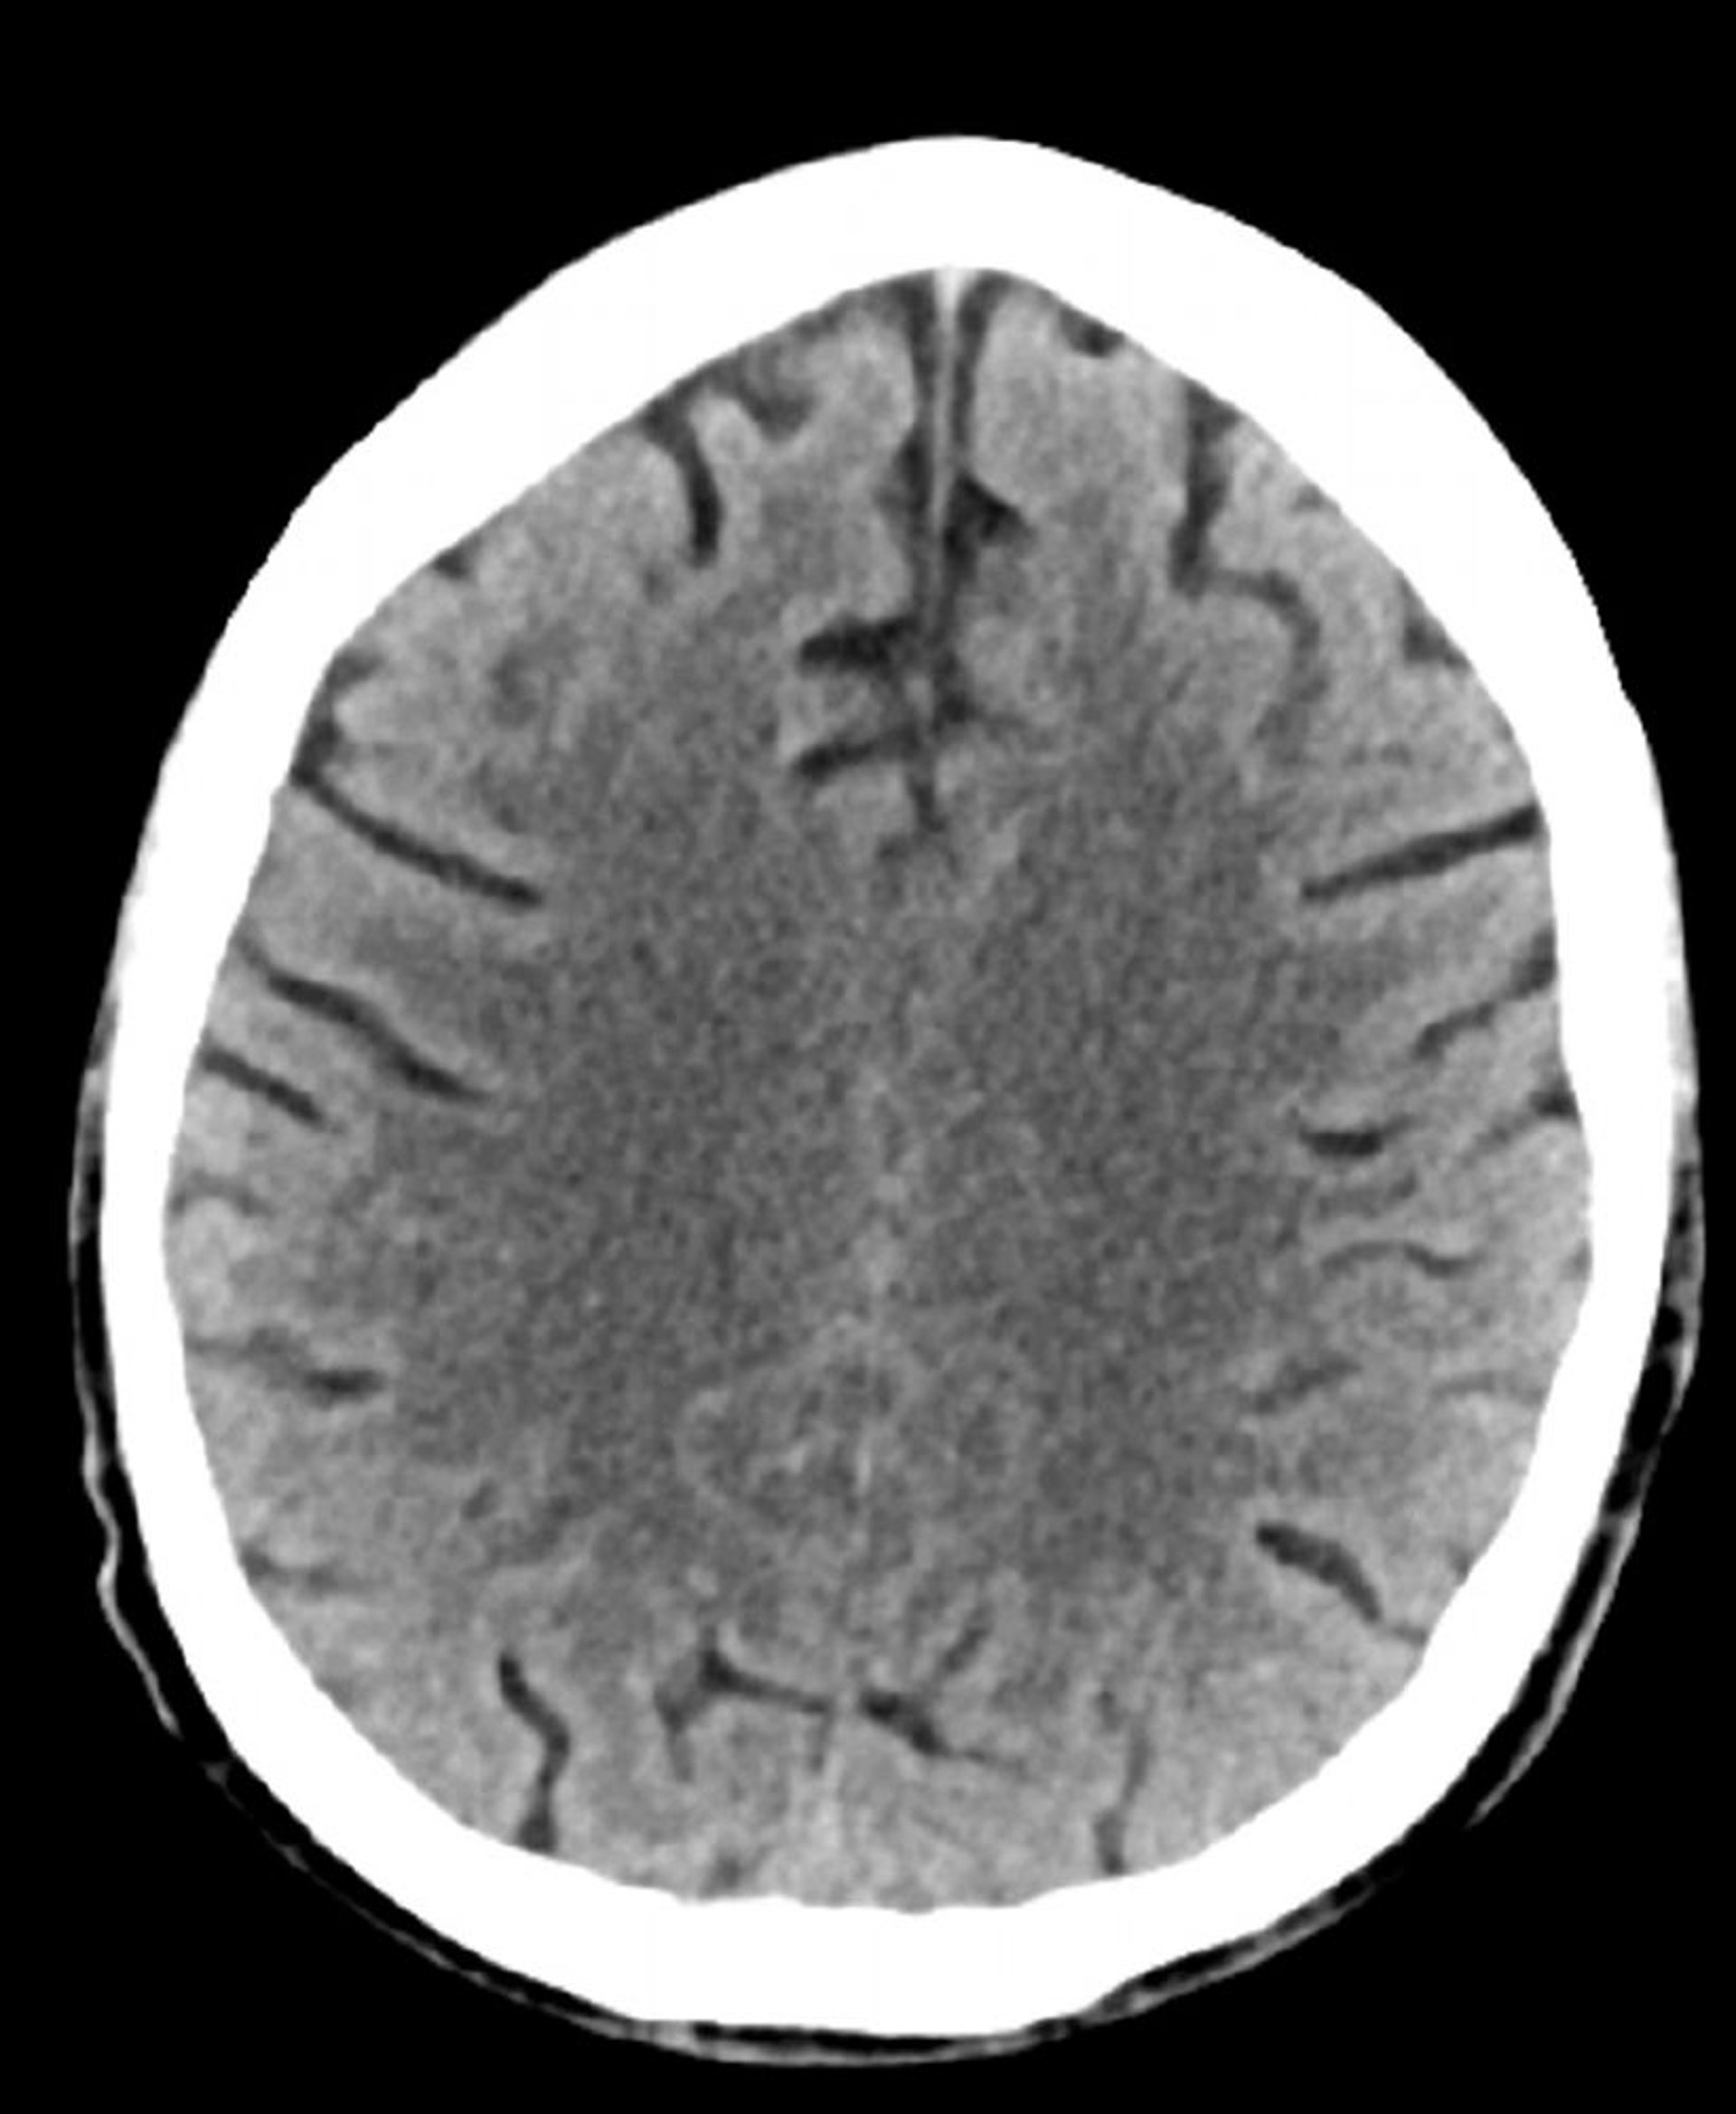

Normal Head CT Scan (Adult, Age 74) – Slide 2

This image is a normal CT scan of the head of an adult aged 74. When compared with the normal CT scan of the head of a 30-year-old, the sulci are larger. These findings are normal in this age group.